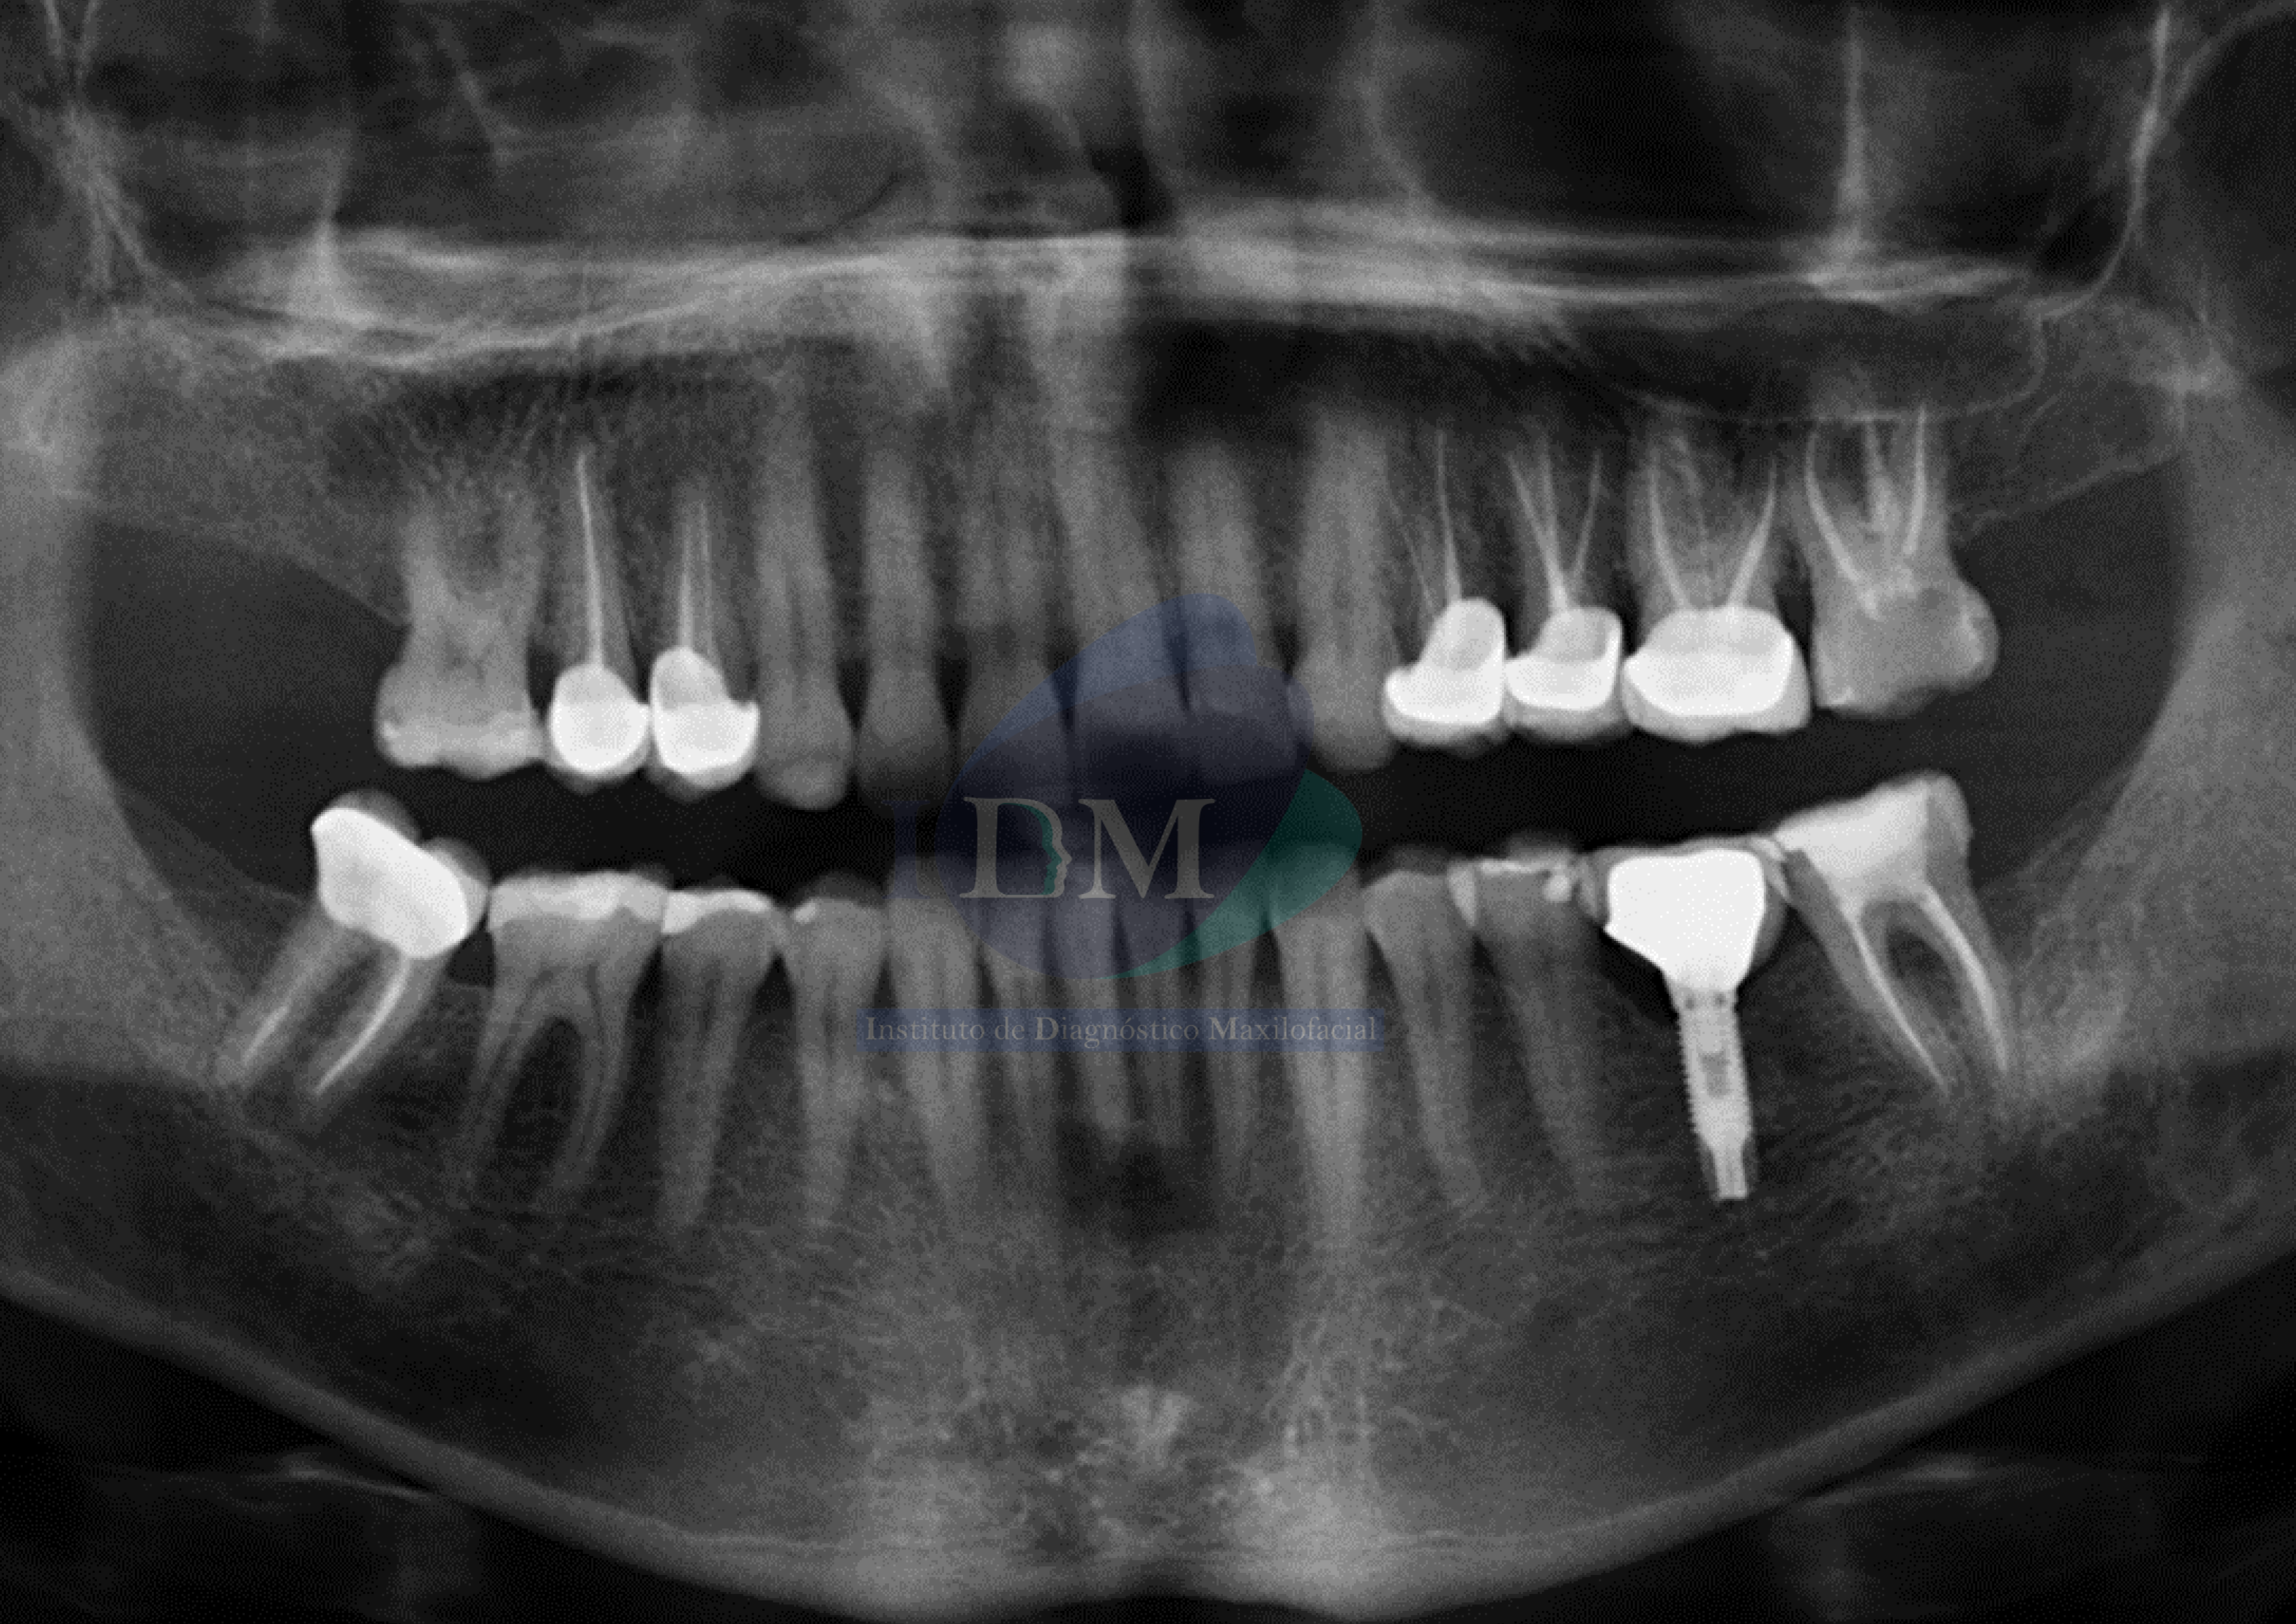

Radiografia Panorámica

A la evaluación de la radiografía panorámica se evidencia múltiples piezas con tratamientos de conductos y múltiples restauraciones. Presentando un implante con prótesis sobre implante en zona de la pieza 36.